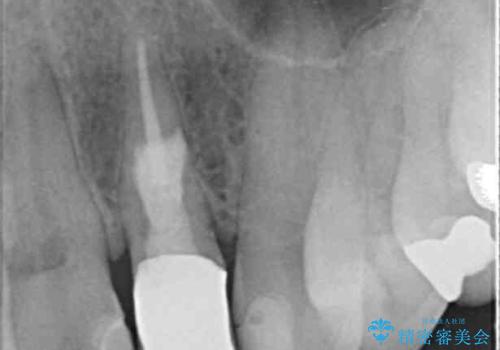

30代女性 矯正中の歯ぐきの腫れ

矯正中に歯が痛くなるのはよくあることですので、こういった際は注意深く経過を観察して自然に緩解するケースを考慮しなくてはなりません。

しかし今回は経過をみる中で不可逆性の炎症を示す症状を呈してきたため、根管治療の介入となりました。

症状は消失し、歯ぐきの腫れもなくなったため、一度矯正に戻っていただき、矯正終了後クラウンにて修復するのがよいでしょう。